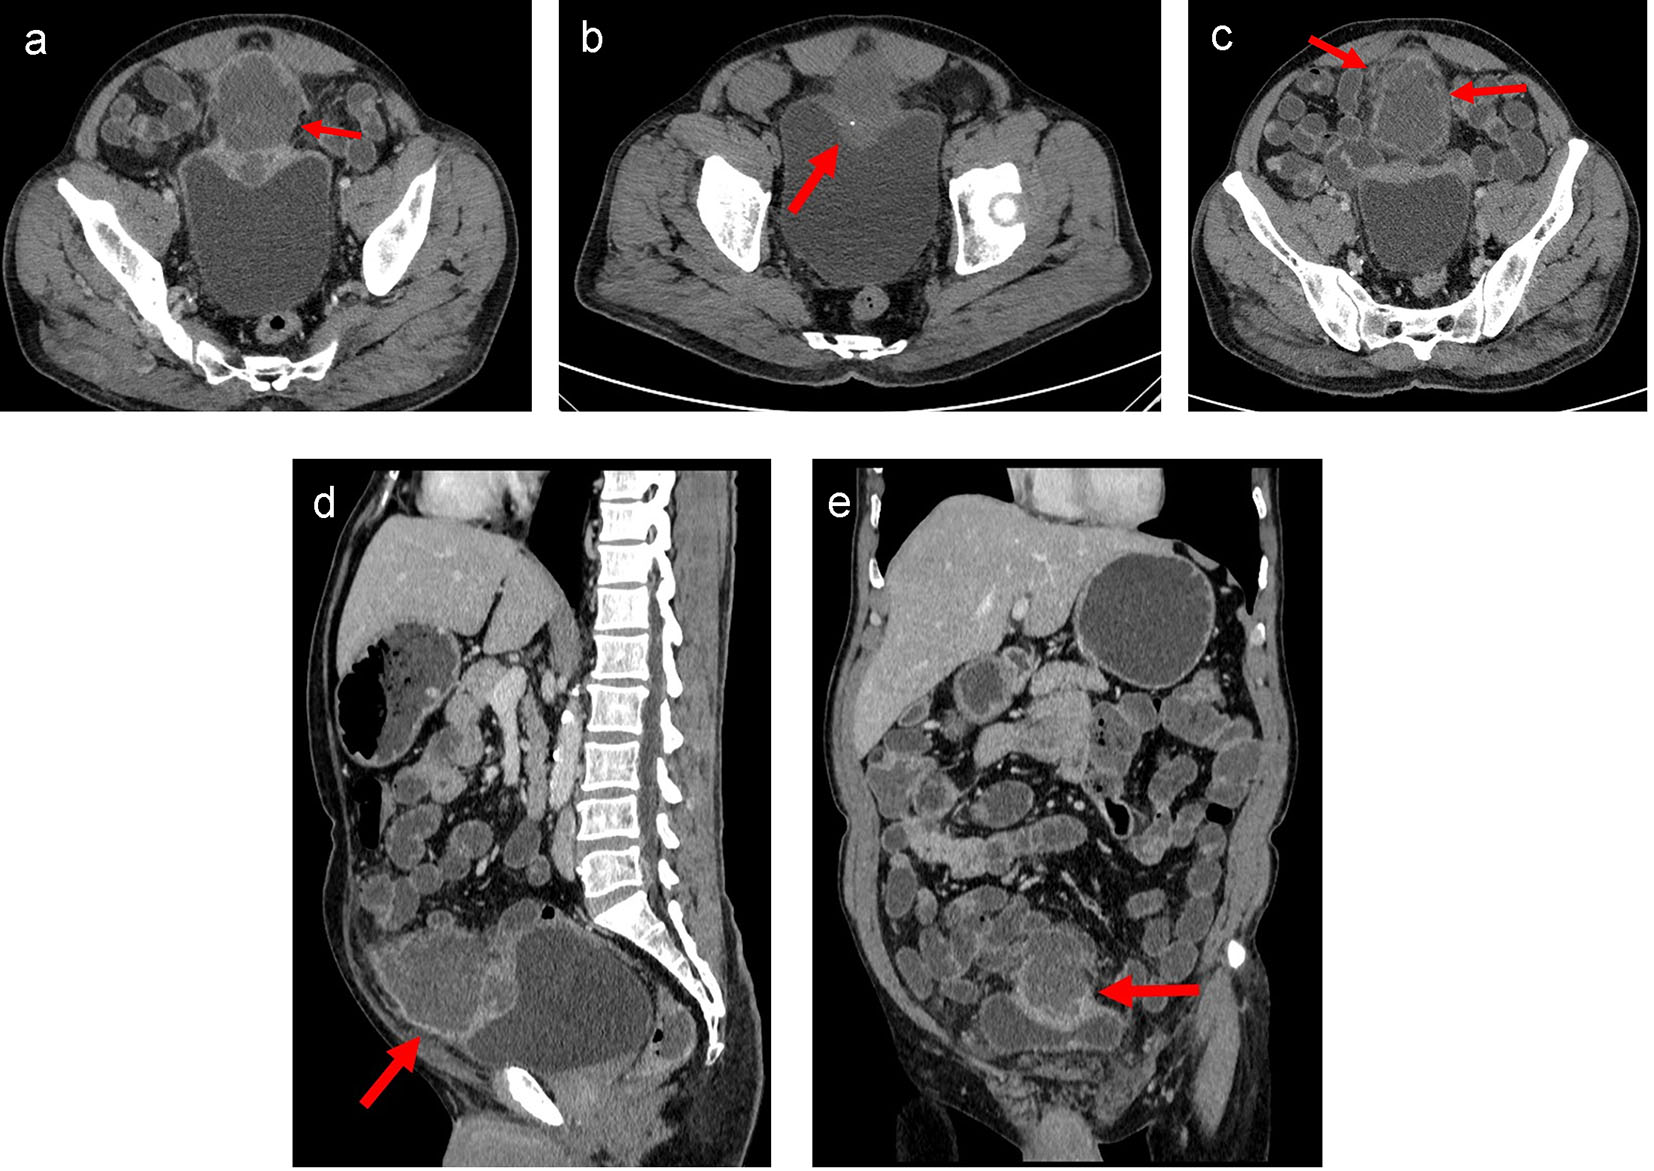

CECT of the abdomen and pelvis showed a moderate sized oval hypo-enhancing mass with thick and irregular peripheral enhancement and central non-enhancing low-attenuation area with ill-defined margins arising from the dome of the urinary bladder with exophytic growth anteriorly (Fig. 2a-e). Moderate thickening of the dome of the urinary bladder was noted for a length of about 6.7 cm. Small focus of calcification was noted in the periphery of the lesion (Fig. 2b). Rest of the bladder wall was normal. Infiltration into the surrounding region with moderate perilesional fat stranding was noted (Fig. 2c). Fat planes with abdominal wall were maintained. Displacement of the ileal gut loops was noted superiorly. The lesion was abutting a short segment of ileal loop. However, no obvious/definite infiltration was noted. A lymph node of size 9 mm short axis was noted in right external iliac region. Few subcentimeter lymph nodes were noted in both external iliac and common iliac regions. Based on the imaging findings, possibility of necrotic urachal remnant neoplastic lesion could not be ruled out.

![]() Click for large image | Figure 2. (a) Axial CT image of lower abdomen in venous phase showed moderate sized oval hypo-enhancing mass (arrow) with thick and irregular peripheral enhancement and central non-enhancing low attenuation area with ill-defined margins arising from the dome of the urinary bladder with exophytic growth anteriorly. Moderate thickening of the dome of the urinary bladder was noted. Rest of the bladder wall was normal. Infiltration into the surrounding region with moderate perilesional fat stranding was noted. Fat planes with recti muscles were maintained. (b) Axial plain CT image of lower abdomen showed a small focus of calcification (arrow) in the periphery of the lesion. (c) Axial CT image of lower abdomen in venous phase at a higher section showed infiltration into the surrounding region with moderate perilesional fat stranding (arrow). (d) Sagittal CT image of abdomen in venous phase showed mass arising from dome of urinary bladder with maintained fat planes with abdominal wall (arrow) and displacement of the small bowel loops. (e) Coronal CT image of abdomen in venous phase showed mass arising from dome of urinary bladder (arrow) with superior displacement of the small bowel loops. |